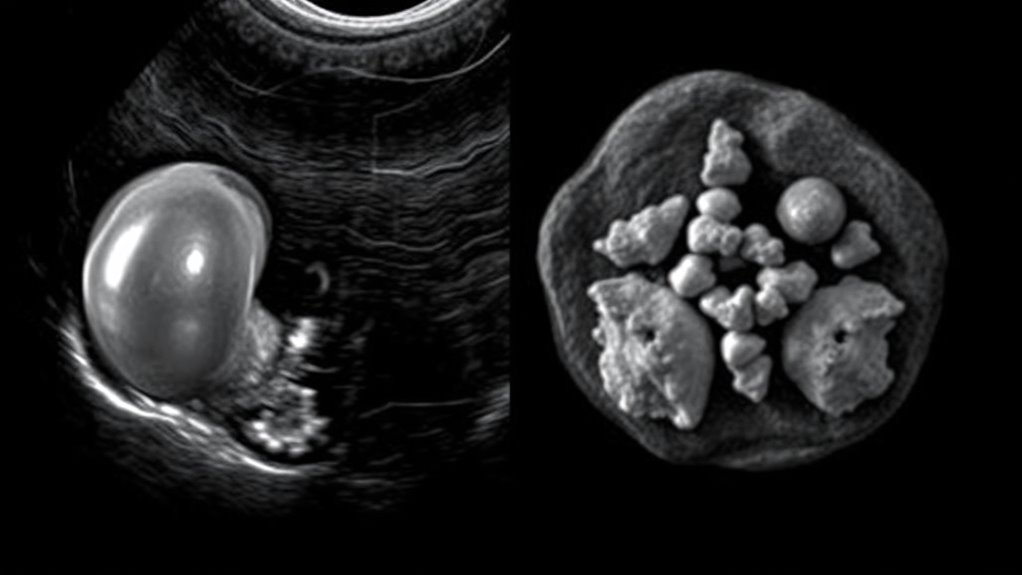

Unterscheidung von zystischen und soliden Massen

Eines der Hauptmerkmale der Ultraschalluntersuchung liegt in ihrer Fähigkeit, zwischen zystischen und soliden Brustmassen schnell und effektiv zu unterscheiden. Dies hilft Ihnen, die Natur der Läsion zu bestimmen und die weitere Behandlung zu lenken. Zystische Läsionen erscheinen typischerweise anechoisch mit klaren, glatten Grenzen und zeigen eine posteriore akustische Verstärkung. Solide Massen weisen oft interne Echos, unregelmäßige oder glatte Ränder auf und können erhöhte Durchblutung zeigen. Um diese zu unterscheiden, achten Sie auf:

- Anechoische, flüssigkeitsgefüllte Erscheinung bei Zysten

- Gut abgegrenzte Ränder, die auf benigne Zysten hinweisen

- Interne Echos oder komplexe Merkmale, die auf solide oder komplizierte Zysten hindeuten

- Erhöhte Durchblutung sichtbar mit Doppler, was auf solide oder verdächtige Läsionen hinweist

Mithilfe dieser Ultraschallmerkmale können Sie Brustmassen genau klassifizieren und entscheiden, ob weitere diagnostische Schritte, wie eine Biopsie, notwendig sind.